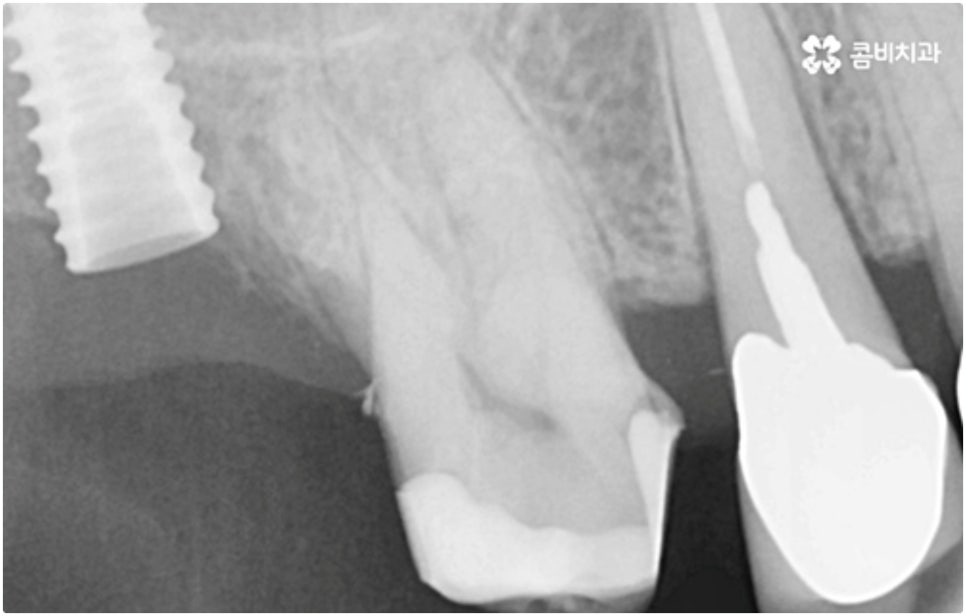

모든 치아가 위치와 모양이 제각각 다른데 특히 어금니는 구강 내 깊은 곳에 있고 주름진 저작면을 가지고 있기 때문에 관리할 때 더욱 주의할 필요가 있습니다. 꼼꼼하게 칫솔질을 해준다고 해도 음식물 찌꺼기가 남게 될 가능성이 높아 충치나 치주염 등 구강 질환이 빈번하게 발생할 수 있기 때문인데요, 이때 빠른 발견으로 초기 대처를 해주지 못하면 내부 신경까지 손상이 깊어져 치아를 발치하고 어금니임플란트 시술을 받아야 할 상황까지 발생할 수 있어요.

구강 질환 때문이 아니더라도 저작 기능의 핵심적인 역할을 담당하고 있어서 외부 충격 (실수로 딱딱한 것을 씹는 일 등) 에 노출될 위험도 큰데요, 만약 부러지고 금이 갈 때 뿌리까지 갈라졌다면 해당 어금니는 살릴 수 없고 인공 치아로 대체해야 할 거예요.

식립 성공률 및 지속적인 안정성을 높이기 위해서는 초기 고정이 잘 이루어져야 하는데 만약에 식립 바탕이 되는 잇몸뼈의 상황이 좋지 않다면 이와 관련된 치료를 먼저 해 줘야 하는 거예요. 예를 들어 치주 질환이 심하다면 이를 깨끗하게 치료해 주는 것이 우선시 되어야 하고, 잇몸뼈의 높이나 밀도 등이 부족한 경우에는 뼈이식 과정을 통해 이를 먼저 보충해 줄 필요가 있어요. 또한 윗어금니가 빠진지 오랜 시간이 지나 이미 골흡수가 일어나고 상악동이 많이 내려와 있다면 상악동 거상술 및 뼈이식을 한 후 임플란트 식립을 진행해야 할 거예요.

이와 같이 상악의 경우 상악동과 비강저(콧구멍 바닥)까지의 거리 및 신경과 혈관분포, 하악의 경우 하치조 신경 및 하치조관과 이공까지의 거리, 주위 조직 등에 대한 면밀한 검진과 파악이 필요하기 때문에 임플란트 시술을 진행할 때 상하악골 및 주변 조직을 해부학적으로 자세히 체크할 수 있는 정밀 장비 및 담당 의료진의 숙련도가 굉장히 중요한 요소라고 할 수 있어요.